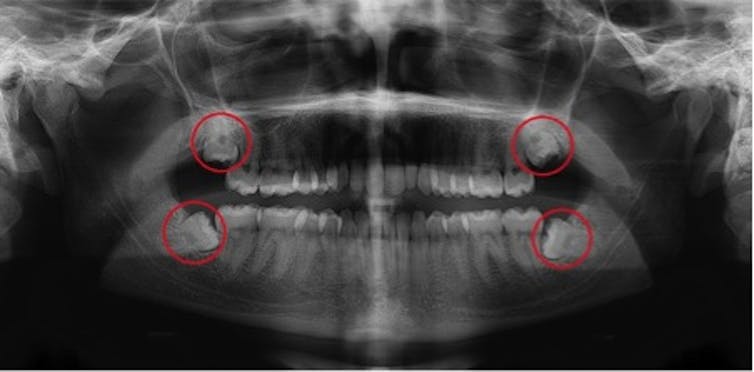

Wisdom teeth are always the teeth furthest back in each quadrant of the mouth. Most people develop four wisdom teeth, but many people may only have three, two, one, or if you are particularly lucky, none.

Anthropologists believe changes in our dietary habits to softer, less abrasive foods have reduced the amount of tooth wear, meaning larger teeth and less room in the jaw. As such, by the time wisdom teeth erupt, there may not be enough space in the jaw for this process to occur normally. The result is impaction, where the tooth emerges at an abnormal angle. This can cause pain for two reasons:

Impacted wisdom teeth never become fully functional, and the best way to manage the problems they cause is to remove the tooth. Because of the tight space and impaction, this is generally a complex surgical procedure that requires a specialist oral and maxillofacial surgeon, who are both doctors and dentists.

In many people, wisdom teeth can erupt and grow normally, and there is no reason to remove them. While everyone should have a routine dental x-ray around the time of wisdom tooth emergence, only people with pain or signs of impaction or abnormalities need removal.